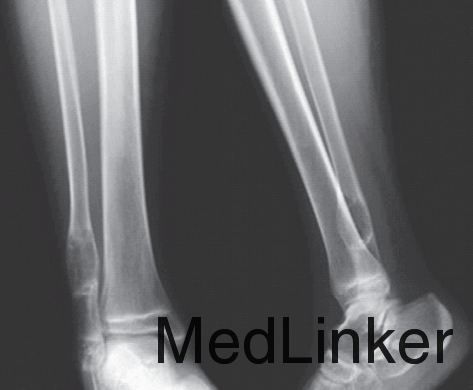

男,15岁,右踝部间断疼痛2年,加重伴右踝部肿胀1周。查体:右外踝上6cm处略肿胀,局部皮温正常,未触及包块,局部压痛明显,右踝关节活动度基本正常。右胫腓骨正侧位平片(图1):右腓骨远端干骺端膨胀性骨破坏,骨密度减低,骨皮质变薄,病灶内有分房,未见骨膜反应及周围软组织影。胫骨中下段髓腔内可见类圆形影,边界清楚,骨皮质无破坏。右踝MRI示:腓骨下段髓腔内显示4.5cm×2cm等T1、短T2异常信号灶,边界清楚,信号不均,其内可见分隔,病灶呈膨胀性生长,骨皮质变薄(图2)。右胫骨中下段髓腔内显示3.7cm×1.7cm椭圆形长T1、T2信号灶,边界清楚,信号均匀,边缘规则,骨皮质连续。结合病史及影像学表现考虑为良性病变,遂在硬膜外麻醉下行右腓骨远端病灶刮除、异体骨植骨、内固定术,右胫骨病灶刮除术。术后病理报告:(1)右腓骨远端髓腔内有5cm×4.5cm×1.3cm肿块。镜下见大片的梭形细胞伴有较多体积较大的多核巨细胞,局部见新生的骨小梁样结构,结合临床,考虑为GCT(图4)。(2)右胫骨远端髓腔内见灰黄色结节肿物,总体积3.5cm×3cm×1cm,镜下显示成熟的脂肪细胞并见增生小血管,结合临床考虑血管脂肪瘤(图5)。术后2周切口愈合良好,无红肿渗出现象,术后3个月患肢行走步态接近正常。术后10个月X线片见腓骨植骨融合,无明显骨破坏,胫骨开窗处可见骨修复(图6)。